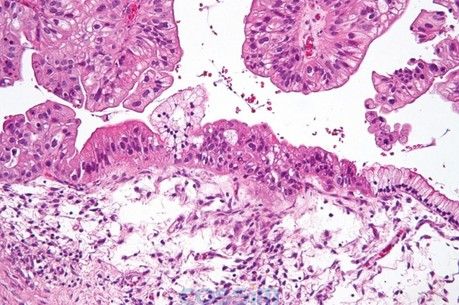

圖解:卵巢癌組織切片:圖為H&E染色后顯微鏡下的低度惡性潛能黏液性卵巢癌組織切片。圖的右方是正常的簡單黏液性上皮細(xì)胞,而圖的左方呈偽復(fù)層纖毛上皮處則被診斷為低度惡性潛能腫瘤細(xì)胞。

圖上方呈葉狀體結(jié)構(gòu)者為上皮細(xì)胞。